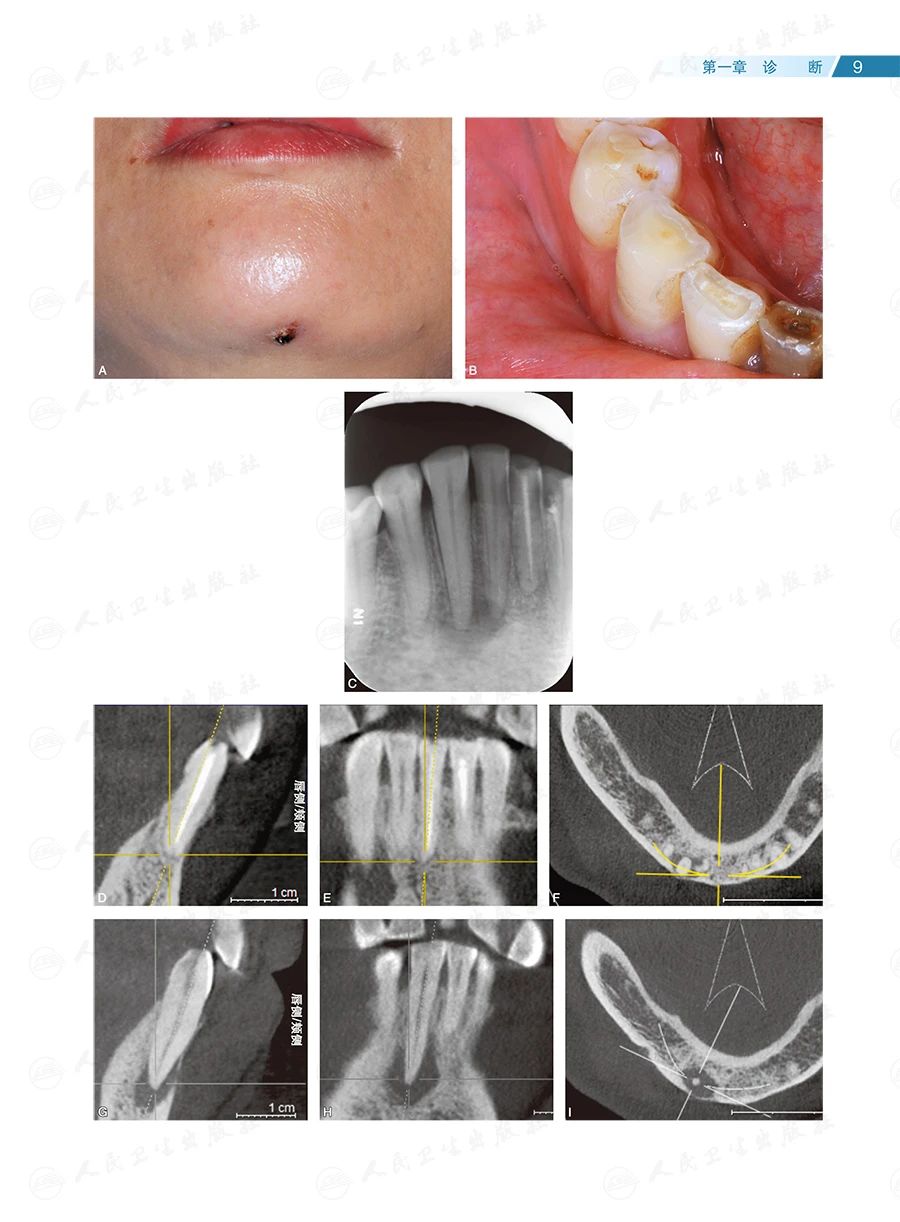

全书共133个临床病例、约1400幅照片,内容全面、图文并茂、形象直观。按照诊断、确定治疗方案和治疗的顺序,全书分为六章:第一章为诊断,主要讨论根尖周透射影、根裂的诊断和鉴别诊断;第二章为治疗方案选择,重点探讨非手术和手术(再)治疗方案的选择;第三章为在体手术治疗,即显微根尖外科,讨论特定牙位和牙根的手术,以及一些复杂疑难牙髓病、根尖周病的手术治疗;第四章为离体手术治疗,即显微意向再植术,全面讨论其适应证;第五章为多学科合作,包括牙髓源性上颌窦炎、联合应用引导性组织再生术(guided tissue regeneration,GTR)、自体牙移植术中的应用;第六章为全文总结,系统阐明牙髓病、根尖周病治疗的整体策略。